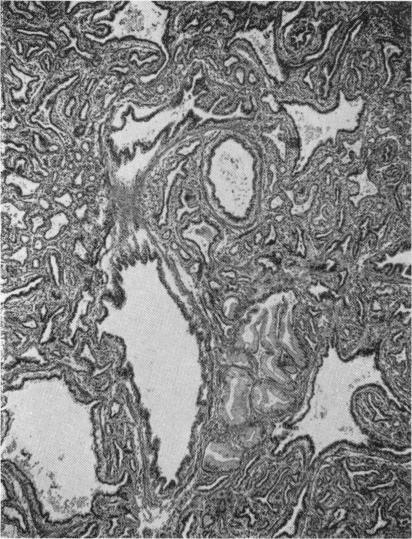

Congenital Adenomatoid Malformation of Lung with Pneumothorax.

Arch Dis Child. 1960 Oct;35(183):475-80. doi: 10.1136/adc.35.183.475.